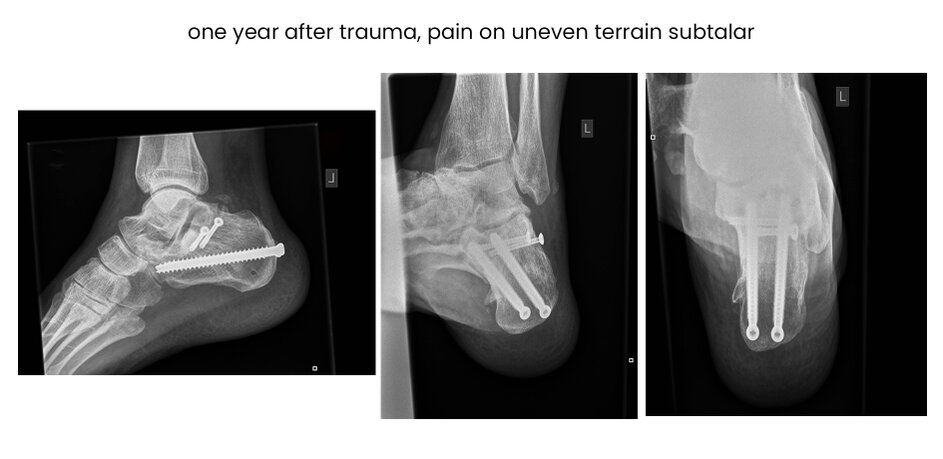

14CE, male 52 y, comminuted, MIT,surgery 2 days after trauma, secundary arthrodesis